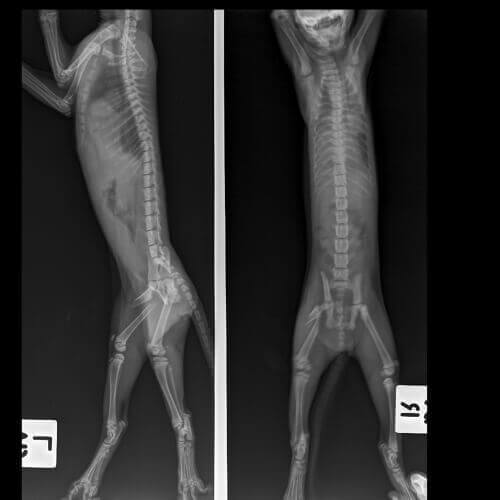

Diagnosen kan kräva några speciella tester som ofta involverar ett eller flera av följande:

- Röntgen.